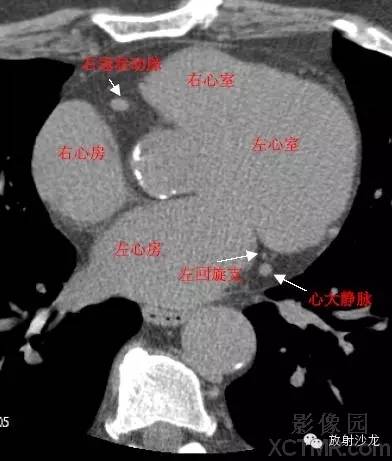

LA -Left Atrium左心房

RA -Right Atrium右心房

LV -Left Ventricle左心室

RV -Right Ventricle右心室

LCX -Left Circumflex Artery左回旋支

RCA -Right Coronary Artery 右冠状动脉

GCV–Great Cardiac Vein心大静脉